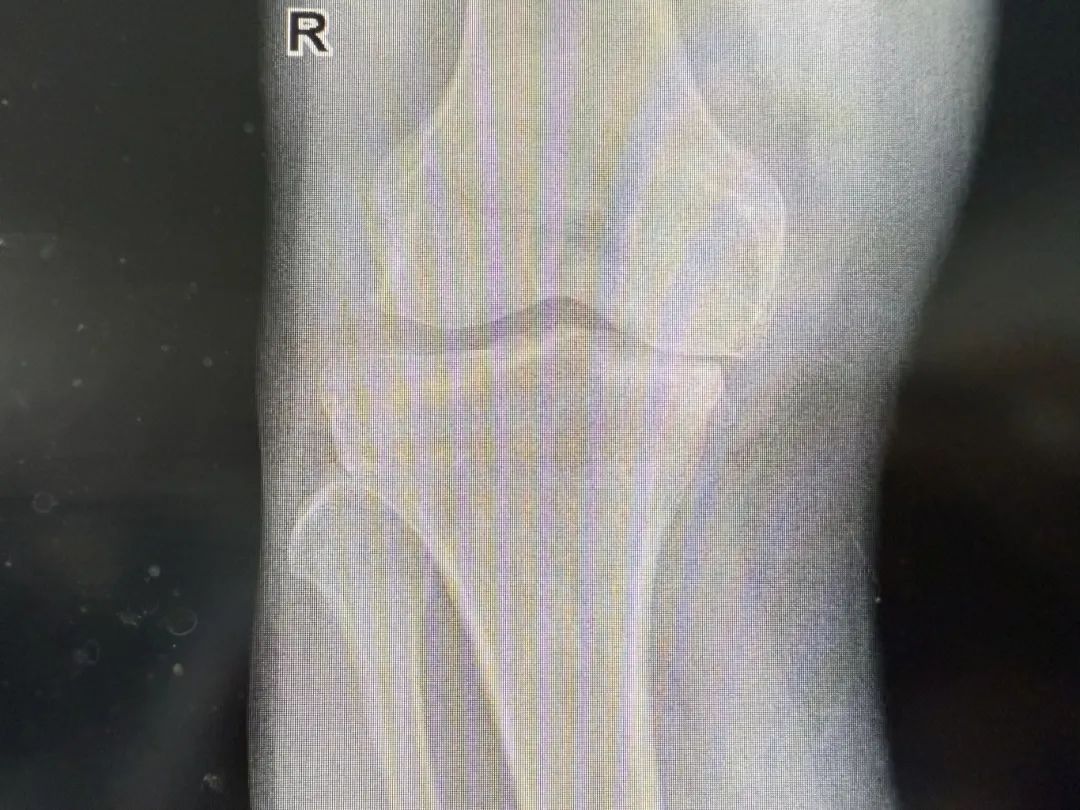

在家人陪伴下,于大叔来到日照市康复医院骨科专家门诊。尹绍猛教授接诊后,详细询问了病史并安排于大叔进行全面细致的体格检查,结合影像学资料进行了深入分析,判断其为严重膝关节骨性关节炎,关节结构破坏严重,保守治疗已无法奏效,全膝关节置换术是恢复其关节功能和行走能力的唯一有效途径。

“考虑到患者年龄和对未来生活质量的需求,我们必须选择一种更持久、更适合他的解决方案。”尹绍猛解释道。经过骨科团队严谨的术前评估和多学科讨论,一个更优的解决方案浮出水面——生物型(非骨水泥)膝关节置换技术。